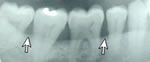

This patient has Periodontitis. Notice the

bone deterioration and uneven level of bone.

Healthy gums and bone.